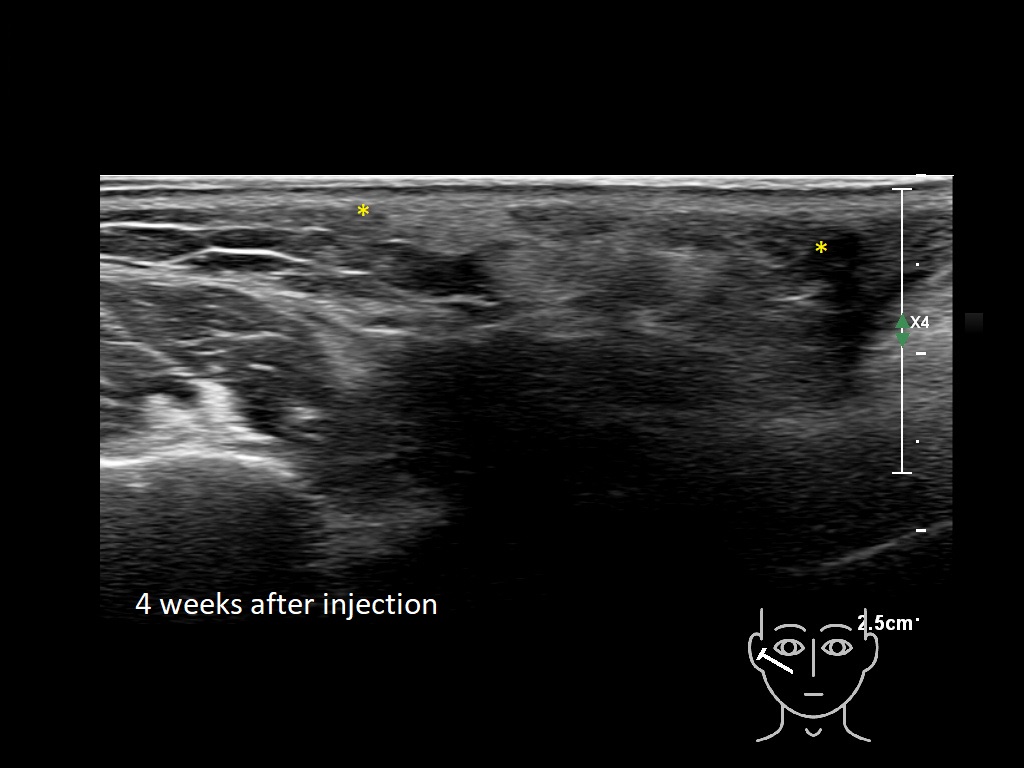

Draw in the image on the right where the fillers are located. To check if your answer is correct, please click on the secondary image.

Draw in the second image below where the fillers are located. To check if your answer is correct, swipe the first image to the right.